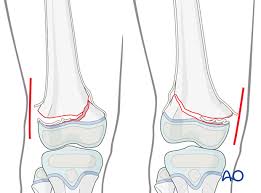

Palpable to either side of the knee joint when it is bent, they are known specifically as the medial and lateral femoral condyles. Sagittal plane fracture of the medial femoral condyle. Damage may also be the result of a direct blow to the knee. The flap is marked by identifying the vascular plexus on the medial condyle and incorporating a component of the network in the flap. Medial femoral condyle fracture study results.

Chondral injuries may accompany an injury to a ligament, such as the anterior cruciate ligament. Your knee mri will often show a: Schatzker i tibia plateau fracture. Osteonecrosis of the medial femoral condyle presents as a sudden onset of pain on the medial side of the knee. Normal irregular ossification of the femoral condyles was present in 66% of the boys and 44 % of the girls 1 in a review of knee radiographs of 147 healthy, asymptomatic children between the ages of 3 and 13 years. However, two of the patients had one or more fractures missed when they first presented. A bone fracture at this location is termed a femoral condyle fracture. According to the hospital for special surgery, the medial femoral condyle is the inside of the knee, and health issues dealing with it can be treated.

Of the six patients who had suffered an isolated fracture of their medial condyle, four of the patients had their fractures diagnosed on the first visit. The lateral condyle was involved in 44 % and the medial condyle in 12 %. It acts to support a significant amount of the patient's body weight. Cartilage can be focally damaged, producing a pot hole in the joint surface, when the knee ligaments are injured. Osteonecrosis of the medial femoral condyle presents as a sudden onset of pain on the medial side of the knee. A bone fracture at this location is termed a femoral condyle fracture. The femoral condyle is a thickened area of the femur just above the knee. One presumed mechanism of injury is a stieda fracture (avulsion injury of the medial collateral ligament at the medial femoral condyle). Root tear (radial tear) of the medial meniscus mild or moderate knee arthritis Coronal plane fracture of the lateral femoral condyle. The lesions were located on the medial femoral condyle in 8 (72.7%) cases and on the medial tibial plateau in 3 cases (27.3%). The medial femoral condyles are the bony protrusions on the inside edge of the bottom of the femur bone in each thigh. Based on the patient's antalgic gait and radiographic findings, the patient was instructed on the proper use of crutches and referred to an orthopaedic surgeon for appropriate management.